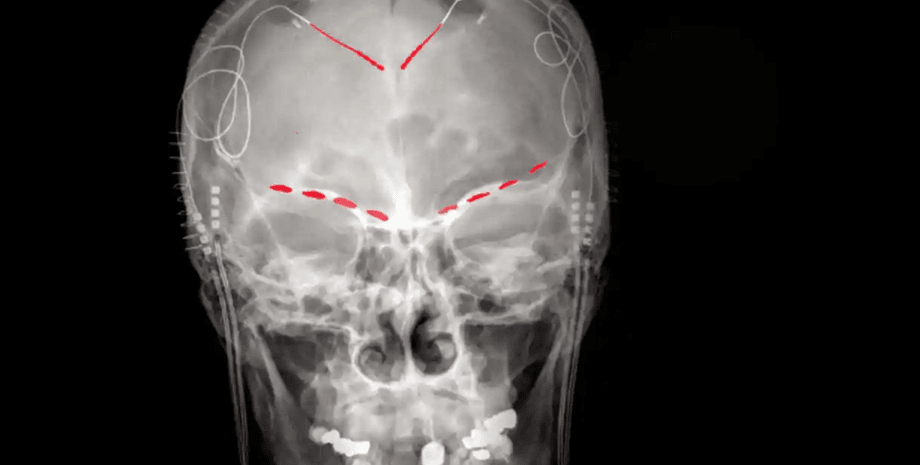

Фронтальный рентген одного из участников исследования, показывающий (красные) имплантированные мозговые электроды | Фото: Prasad Shirvalkar

В своем новом исследовании Ширвалкар и его команда стратегически разместили электроды у четырех пациентов, страдающих от непрекращающейся хронической боли вследствие инсульта или потери конечностей. Эти приспособления помогали пациентам фиксировать активность мозга в передней поясной коре (ППК) и орбитофронтальной коре (ОФК) с помощью удобного устройства дистанционного управления.